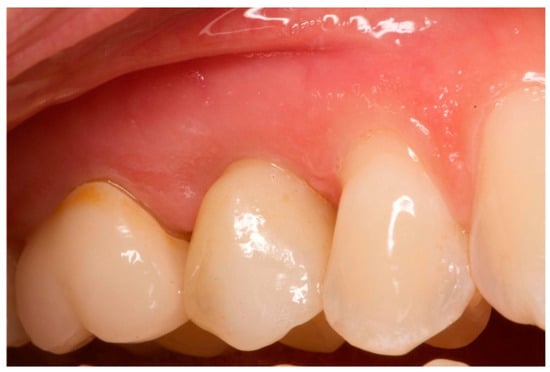

Figure 1.

Vestibular view prior to implant insertion of tooth 1.5.